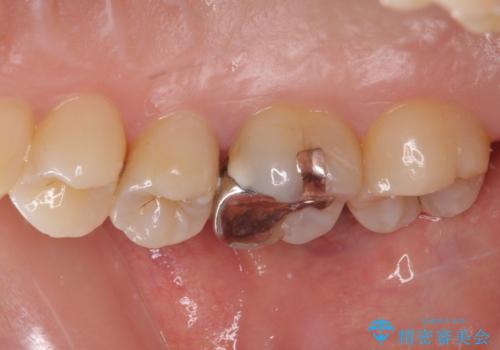

- 冷たいものがしみるとのことで来院された患者様です。

レントゲン写真より、第一小臼歯にやや大きい虫歯があることが分かりました。

症状などから診断したところ、神経を取る可能性は低いと考えられたため、セラミックインレーによる修復治療を行うこととしました。

奥の大臼歯にもむし歯があったので、一緒に処置を行いました。